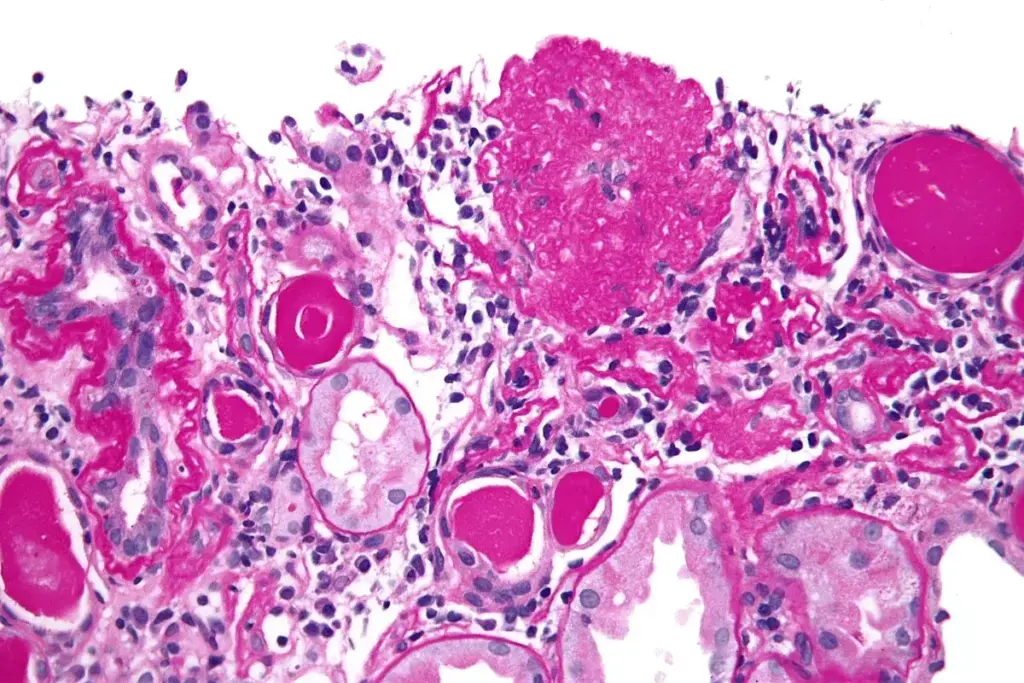

The Three Layers of the Filtration Barrier

The glomerulus filters blood well thanks to a special barrier. This barrier has three main layers:

- fenestrated endothelial cells with pores of 70 to 100 nanometers,

- the glomerular basement membrane made of type IV collagen, laminins, and proteoglycans,

- specialized podocytes with foot processes and slit diaphragms.

These layers filter blood well, keeping important proteins and blood cells in.

The Bowman’s capsule is close to the glomerulus. It’s covered by podocytes that let fluid into the nephron. This connection is key for blood filtration and collecting the filtrate, which becomes urine.